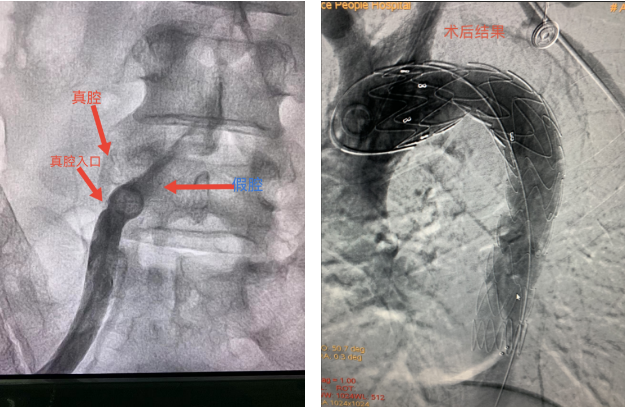

根据患者病史、体征及相关检查,完善胸腹主动脉CTA检查,结果提示:主动脉夹层DebakeyⅢ,胸腹段假腔大于真腔,假腔基本完全造影剂填充,假腔向下延及双侧髂外动脉近端,患者的病情已十分的严重,有手术指征。主动脉夹层,通俗讲就是主动脉上鼓起了一个像“瘤子”一样的东西,如果血压过高,主动脉容易从这里“溃堤”。这种疾病危险性非常高,时间久了,裂口会越撕越大,累及心脑肝肾等主要器官,甚至出现猝死。省心血管病医院九科欧阳长生团队,就患者的病情进行术前讨论,布置精密的手术操作计划,与家属进行充分的沟通,于入院次日在局麻下行主动脉覆膜支架腔内隔绝术。

因患者主动脉破口降主小弯侧,破口大,全程假腔大真腔极小,远端破口多,夹层累及双侧髂动脉,左肾、腹腔干真假腔供血,右肾及肠系膜真腔供血,手术难度大。手术过程非常紧张,功夫不负有心人,终于在右髂探寻到极小真腔影,在JR导管下泥鳅及J型都无法进入,欧阳长生灵机一动改用PTCA导丝进入,小心造影证实真腔后建立轨道,顺利完成隔绝,患者术后情况良好,返回病房。

欧阳长生总结:上下都被假腔挡道情况下术中操作要极为轻柔,轻柔冒烟寻找真腔入口,JR导管可调整方向,加PTCA导丝可以进入小腔。